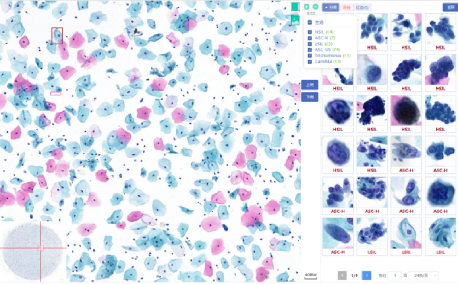

Artificial intelligence is applied based on Deep Convolutional Neural Networkd (DCNN) to retrospectively

analyze cervical liquid-based cytology samples to confirm its feasibility in clinical practice.

Efficient method to detect suspicious

cells in WSI, validate model with a large

number of slides

Graded lesion cells, count cell quantity

automatically

Whole-slide analysis, high TPR, slide

quality intelligent assessment

B/S architecture, convenient access,

strong scalability

Support local and cloud deployment